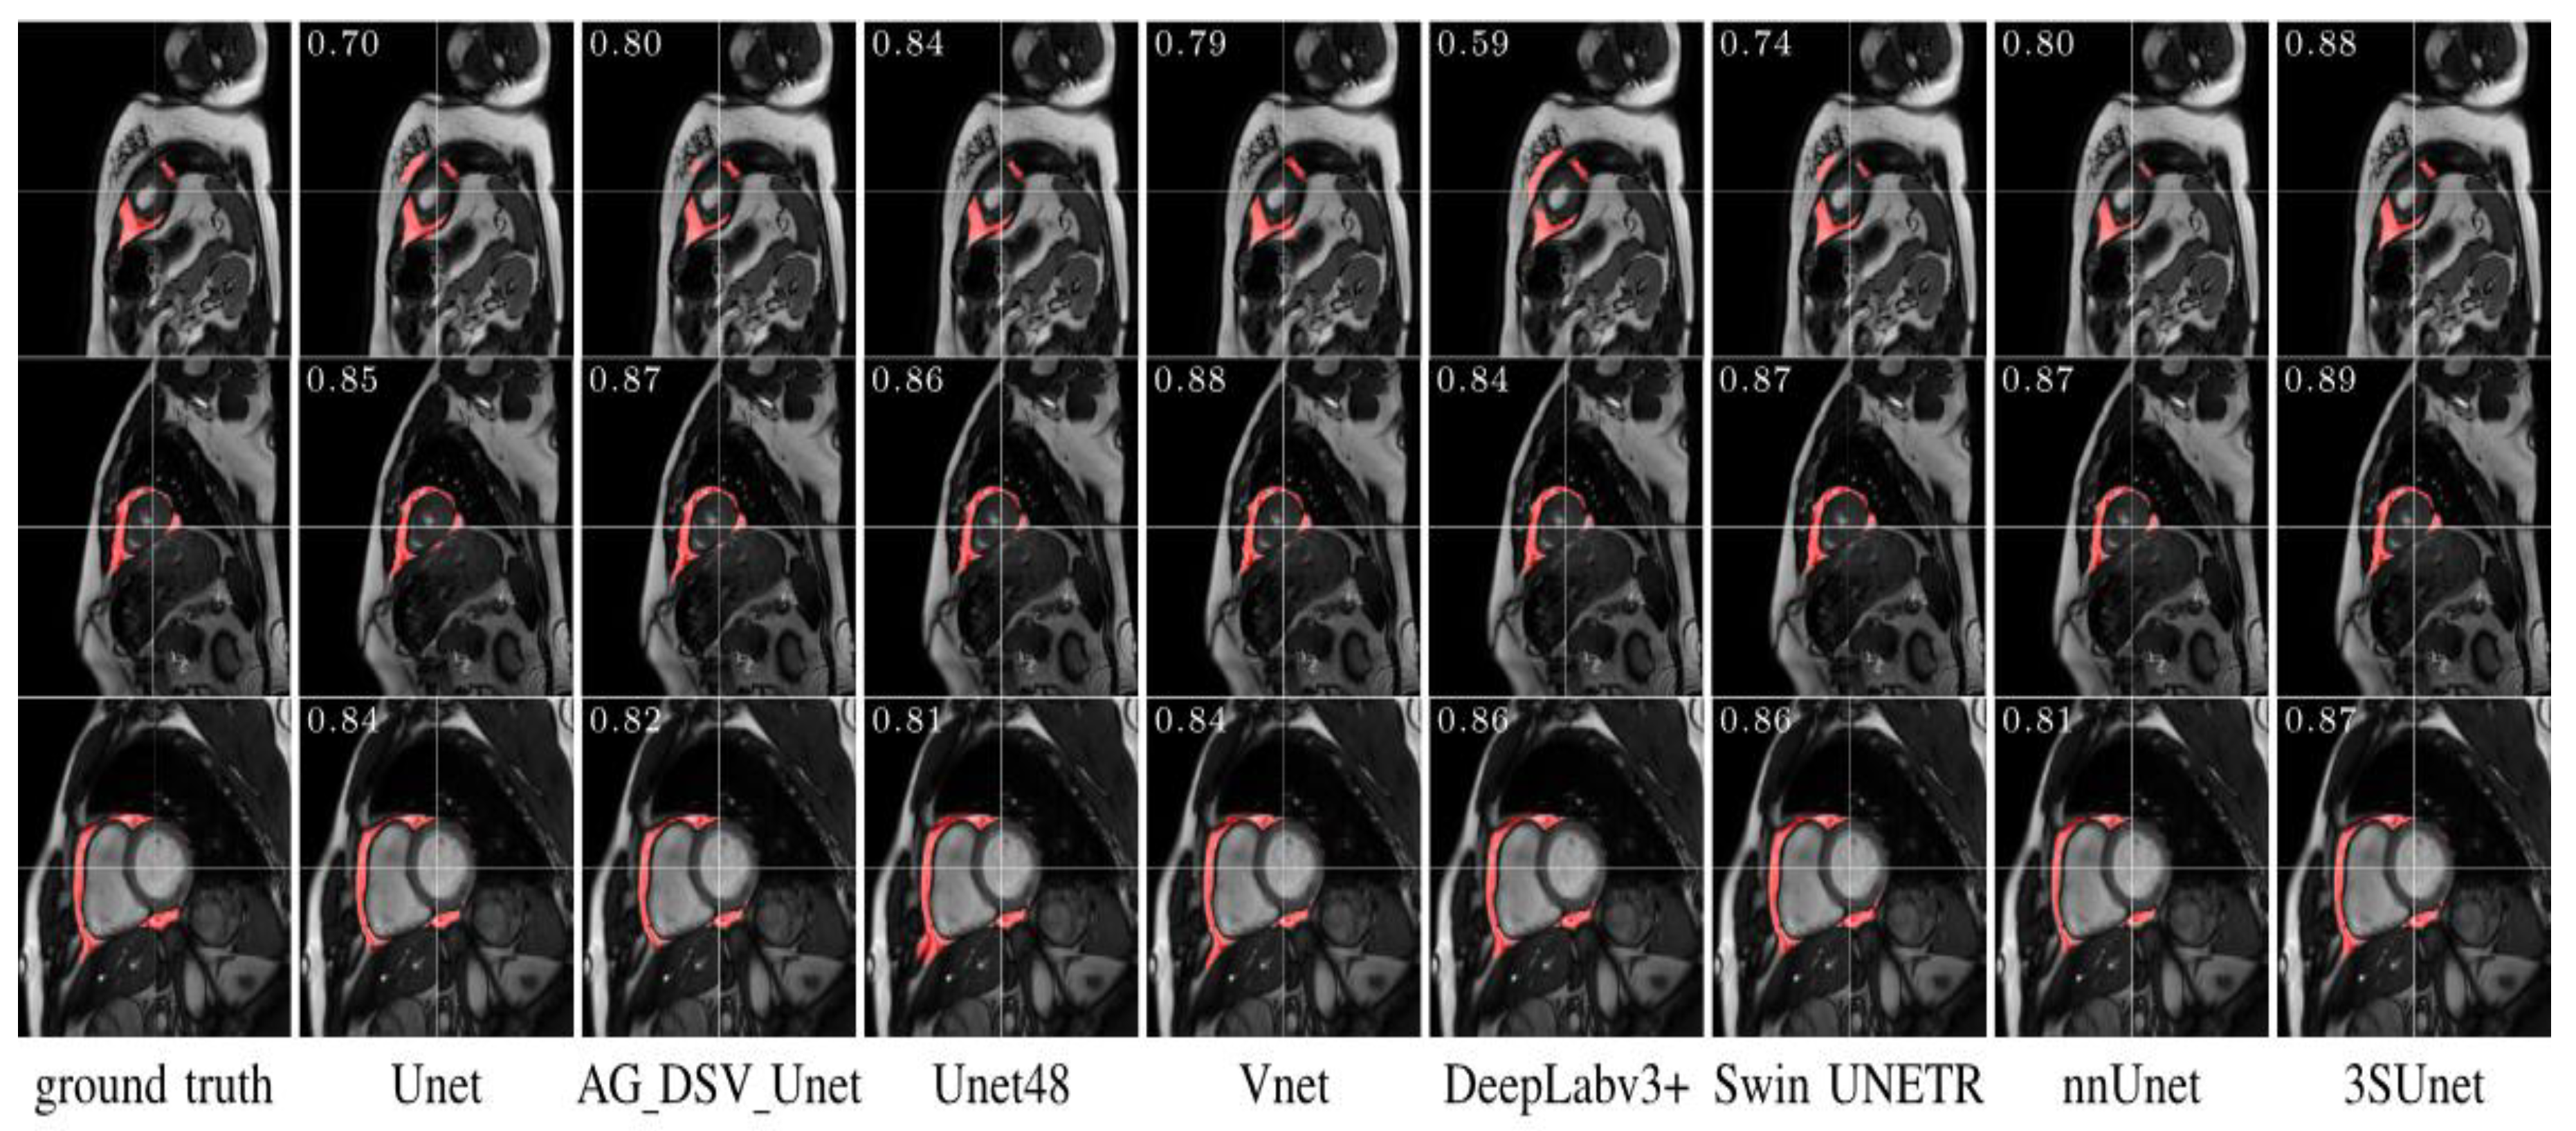

- Chen, S.; An, D.; Feng, C.; Bian, Z.; Wu, L.M. Segmentation of Pericardial Adipose Tissue in CMR Images: A Benchmark Dataset MRPEAT and a Triple-Stage Network 3SUnet. IEEE Trans Med Imaging. 2023, 42, 2386–2399. [Google Scholar] [CrossRef]

- Feng, F.; Carlhäll, C.J.; Tan, Y.; et al. FM-Net: A Fully Automatic Deep Learning Pipeline for Epicardial Adipose Tissue Segmentation. In Statistical Atlases and Computational Models of the Heart. Regular and CMRxRecon Challenge Papers; Notes in Computer Science; Camara, O., Puyol-Antón, E., Sermesant, M., et al., Eds.; Switzerland: Springer Nature, 2024; Volume 14507, pp. 88–97. [Google Scholar] [CrossRef]

- Daudé, P.; Ancel, P.; Confort Gouny, S.; et al. Deep-Learning Segmentation of Epicardial Adipose Tissue Using Four-Chamber Cardiac Magnetic Resonance Imaging. Diagnostics. 2022, 12, 126. [Google Scholar] [CrossRef]

- Kulasekara, M.; Dinh, V.Q.; Fernandez-del-Valle, M.; Klingensmith, J.D. Comparison of two-dimensional and three-dimensional U-Net architectures for segmentation of adipose tissue in cardiac magnetic resonance images. Med Biol Eng Comput. 2022, 60, 2291–2306. [Google Scholar] [CrossRef]

- Fulton, M.R.; Givan, A.H.; Fernandez-del-Valle, M.; Klingensmith, J.D. Segmentation of epicardial adipose tissue in cardiac MRI using deep learning. In: Gimi, B.S.; Krol, A.; eds. Medical Imaging 2020: Biomedical Applications in Molecular, Structural, and Functional Imaging. SPIE; 2020, 25. [CrossRef]